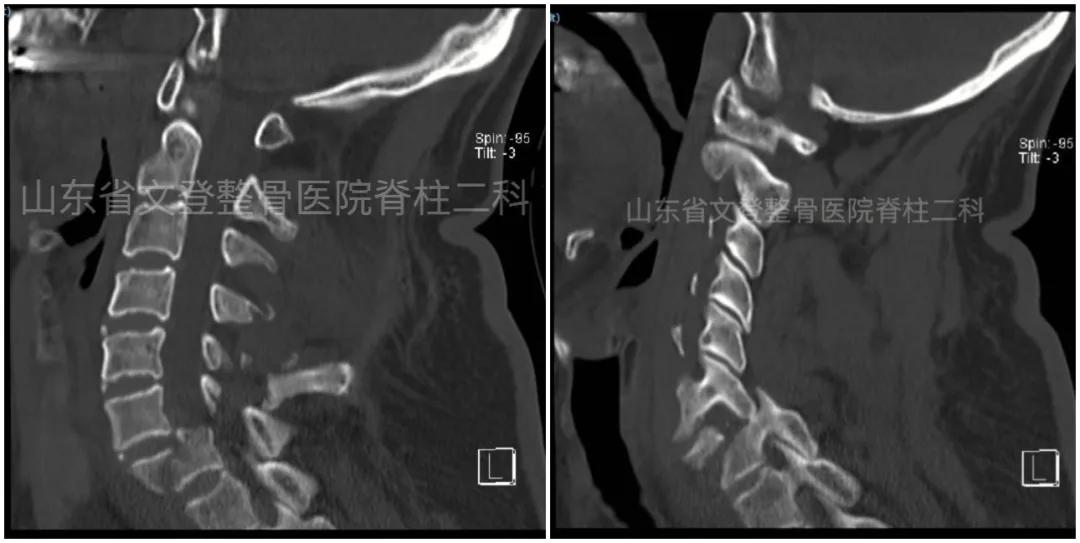

急诊科王英华主任与邢元丽主治医师争分夺秒,立刻详细询问患者病史,仔细查体,考虑到患者为以颈椎骨折脱位并截瘫为主要诊断的多发伤,短时间内可能病情迅速恶化,甚至出现生命危险,需要紧急进行颅脑、肺部及颈部等重要脏器的辅助检查明确诊断,此时患者家属还未到达医院,但与死神赛跑刻不容缓。在紧急向CT、MRI、彩超、新型冠状病毒核酸检测等相关科室讲述患者危重病情后,相关科室大力配合,第一时间明确了主要诊断:1.颈椎骨折脱位并截瘫(C6、C7);2. 胸椎爆裂骨折(T8、9、10);3.脊髓损伤;4.硬膜下积液(双额及左颞);5.双侧多发肋骨骨折(右侧6-8及左侧6-10);6.双侧气胸;7.双侧胸腔积液;8.双侧肺不张等。

术前颈椎CT(矢状位)

术前颈椎MRI(矢状位) 术前胸椎CT(矢状位)